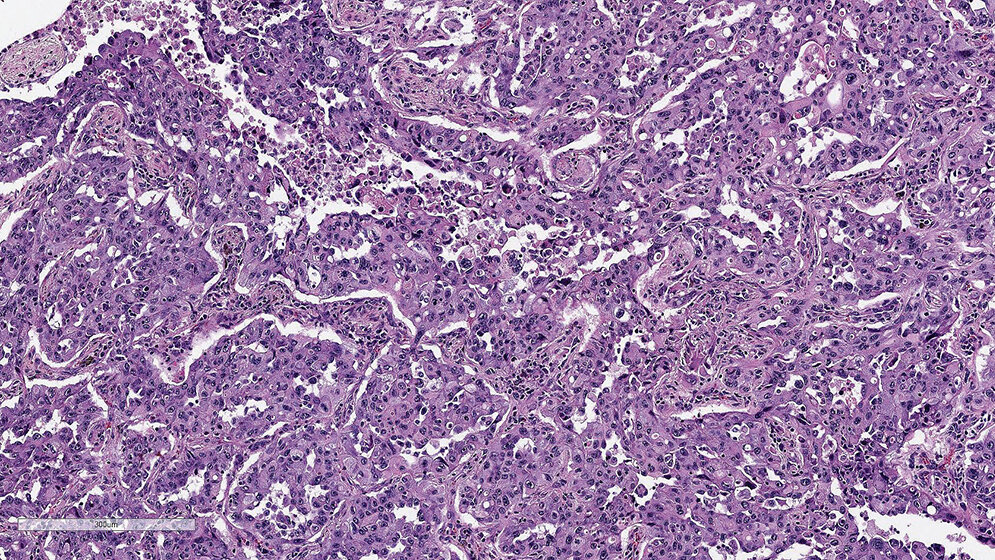

Die qualitätsgesicherte Testung von Biomarkern ist ein wichtiger Bestandteil der modernen Pathologie und eine zentrale Grundlage in der onkologischen Behandlung. Insbesondere die zuverlässige Bestimmung von prädiktiven Biomarkern gewinnt seit Jahren immer mehr an Bedeutung für Ärzte und Patienten. Mit der Zulassung von Wirkstoffen, die das Immunsystem aktivieren können, sogenannten Checkpoint-Inhibitoren, ist der PD-L1 (Programmed cell death 1 ligand)-Status als Biomarker zur Therapieauswahl in den Fokus gerückt. Die Interaktion des PD-1 (Programmed cell death protein 1) mit seinem Liganden PD-L1 dient dabei als Angriffspunkt in der Immunonkologie. Bei der Etablierung eines neuen Biomarkertests gibt es viele Chancen, aber auch einige Herausforderungen für das histologische Labor und den auswertenden Pathologen. Insbesondere die Etablierung von geeigneten IHC-Färbeprotokollen spielt dabei eine zentrale Rolle. In dieser und in den nächsten Ausgaben werden die Färbeprotokolle zur Etablierung und Validierung des PD-L1-Antikörpers unter der Verwendung des Klons E1L3N® der Firma Cell Signaling auf den 4 Plattformen Dako Autostainer Link 48, Dako Omnis, Ventana BenchMark Ultra und Leica Bond III beschrieben.

The quality-assured testing of biomarkers is an important part of modern pathology and a central basis in oncological treatment. In particular, the reliable determination of predictive biomarkers has been gaining increasing importance for doctors and patients for years. With the approval of pharmaceuticals that can activate the immune system, so-called checkpoint inhibitors, the PD-L1 (Programmed cell death 1 ligand) status has become a biomarker for patient selection. The interaction of the PD-1 (Programmed cell death protein 1) with its ligand PD-L1 serves as a target in immuno-oncology. There are many opportunities in estab-

lishing a new biomarker test, but there are also some challenges for the histology lab and the evaluating pathologist. In particular, the establishment of suitable IHC staining protocols plays a central role. In this and the next editions, the staining protocols for the establishment and validation of the PD-L1 antibody using the clone E1L3N® (Cell Signaling) on the 4 platforms Dako Autostainer Link 48, Dako Omnis, Ventana BenchMark Ultra and Leica Bond III will be described.